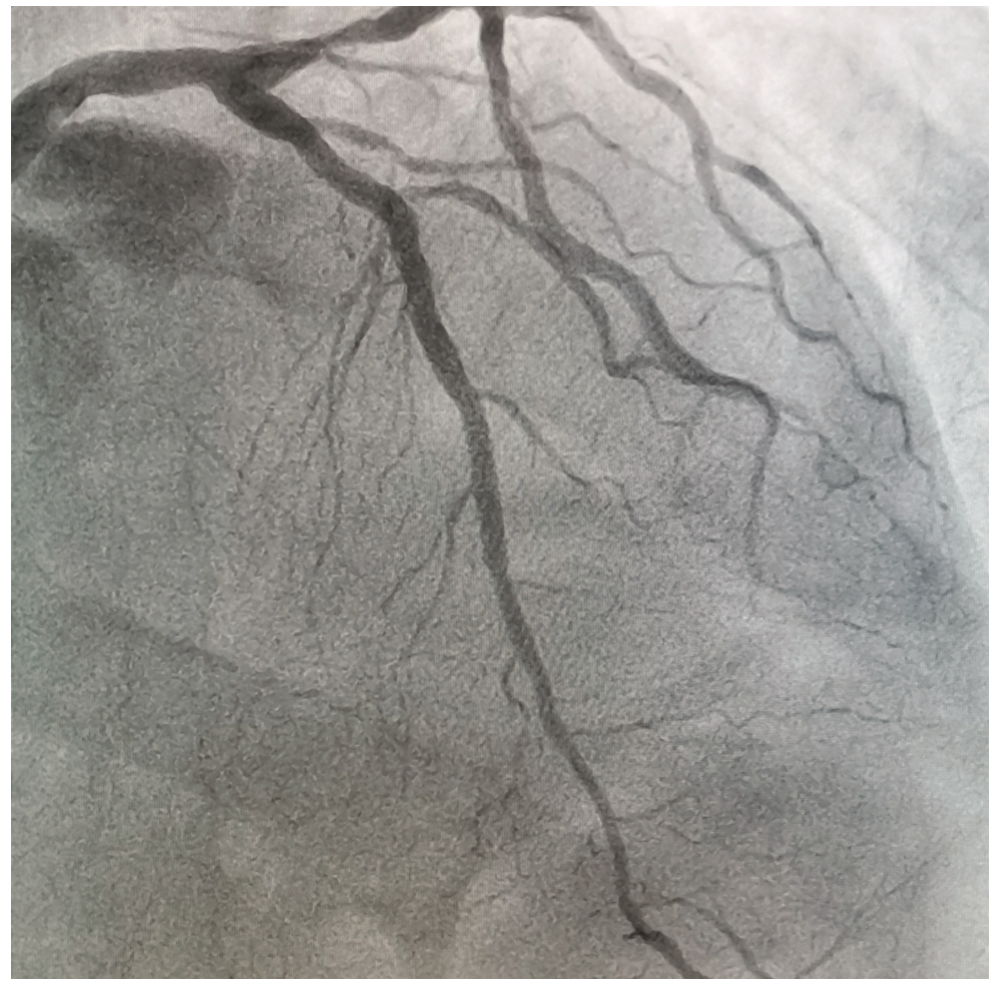

A 69-year-old male with cardiovascular risk factors including hypertension and a sedentary lifestyle presented with typical angina lasting more than 20 minutes. An initial ECG showed de Winter’s pattern (Figure 1) and biomarkers showed a troponin of 12 ng/mL. The patient was then transferred to our center for primary percutaneous coronary intervention. He did not receive thrombolysis, because he was transferred to a center with interventional capacity in less than 2 hours. Upon arrival, a new electrocardiogram was performed where a Wellens’ syndrome type B pattern was observed (Figure 2), suggesting spontaneous reperfusion. The coronary angiogram showed a 99% lesion in the union of the proximal segment with the middle of the LAD with TIMI-3 flow (Figure 3, Video 1). Primary percutaneous coronary intervention with drug-eluting stent implantation was performed, with the final result (Figure 4, Video 1) demonstrating TIMI-3 flow and TIMI myocardial perfusion (TMP) 3.

Video 1. Coronary angiography demonstrating a sub-occlusive lesion at the junction of the proximal and middle segments of the left anterior descending coronary artery.